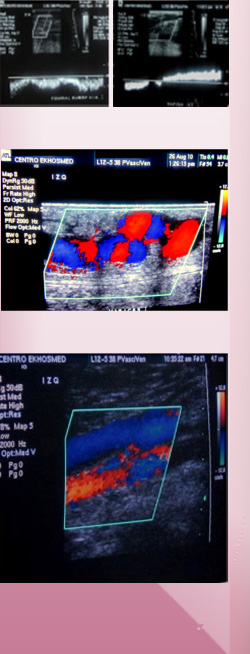

El Eco-Doppler venoso es actualmente la herramienta de trabajo más precisa y necesaria en el estudio diagnóstico de la patología venosa, tanto en la exploración de la insuficiencia  venosa y las várices, como en el diagnóstico de la trombosis venosa.

El más común es el estudio de las venas de las piernas, pero también se pueden estudiar otras localizaciones.